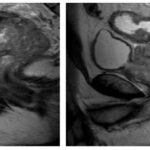

Imágenes de resonancia magnética